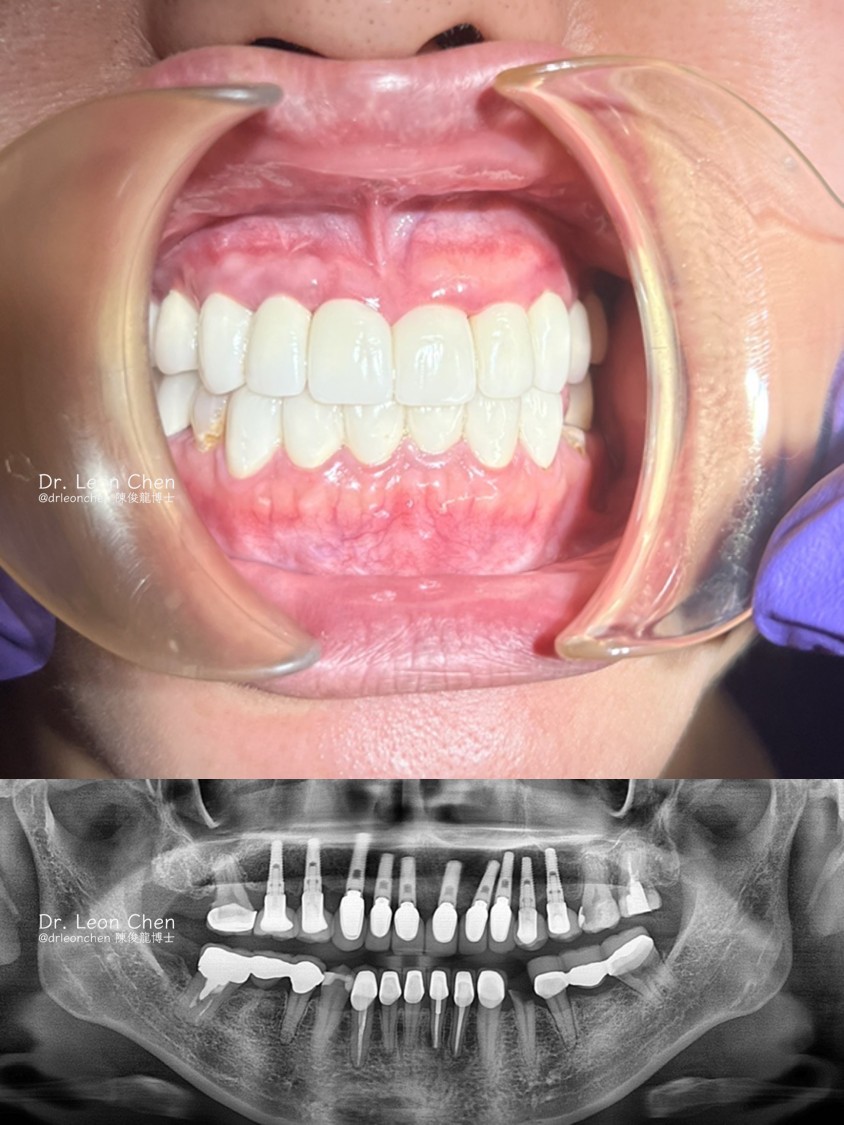

跨越 15年的特殊案例

2008年一位從俄亥俄州(Ohio)飛到加州找陳博士植牙的患者。

手術完成後,由於距離遙遠,期間他完全沒有回來保養與回診。

2023年(整整15年後),他突然出現在陳博士台北駐診的診所,特地來打個招呼。

這15年來完全沒有回診保養的他,情況如何?

臨床檢查顯示,患者沒有牙齦探測出血(No bleeding upon probing),代表著植體周圍組織依然非常健康,沒有紅腫現象,也沒有一般植牙常見的牙肉擠壓。

照片中呈現的,全都是患者真實且自然的牙齦組織。

從2008到2023年,長達 15 年的追蹤(15 years follow up),再次驗證了手術精準度帶來的價值。

看著患者依然健康的笑容,這正是植牙手術追求的最高境界:極致的長期穩定與自然。